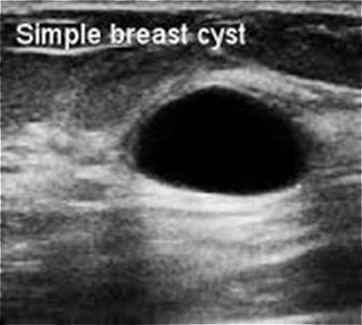

β) Για να διερευνήσουμε τη σύσταση ενός ογκιδίου, συμπαγούς ή κυστικής μορφής (εικόνες 1,2,3) που ψηλαφάται ή φαίνεται μαστογραφικά και να πάρουμε περισσότερες πληροφορίες γι’ αυτό (περίγραμμα, μέγεθος, απόσταση από το δέρμα, αγγείωση).

(Εικόνα 2: Υπερηχογραφική εικόνα κύστεως του μαστού)